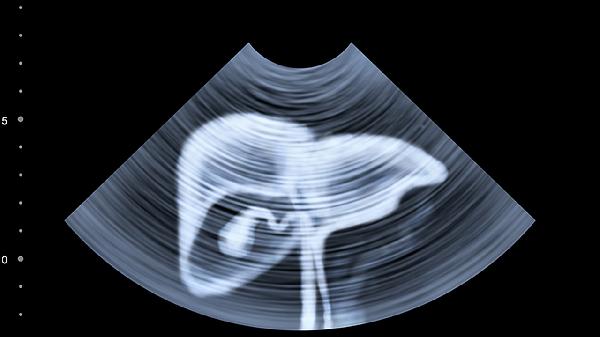

進行肝功能檢查前應保持空腹8-12小時,避免高脂飲食和飲酒。慢性肝病患者建議每3-6個月復查,異常指標需結合腹部超聲等檢查綜合判斷。日常需保持規(guī)律作息,控制體重,避免濫用藥物,肝炎病毒攜帶者應按醫(yī)囑定期監(jiān)測肝功能變化。